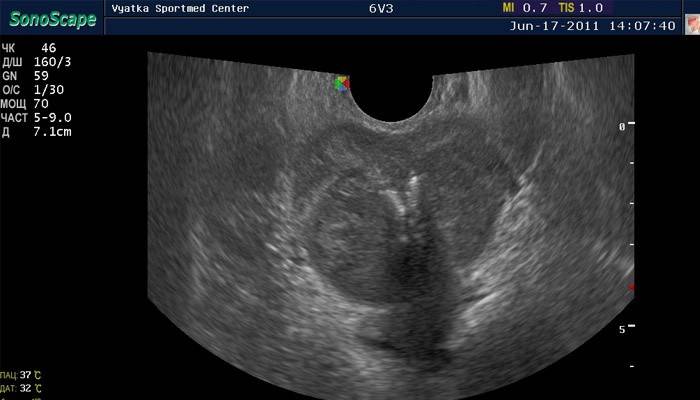

O procedimento é realizado de maneira diferente da ultrassonografia abdominal convencional. Este estudo não causa desconforto. A ultra-sonografia retal da próstata é realizada com a introdução de um sensor especial no reto. Tenha em mente que os aparelhos modernos são muito compactos em comprimento e diâmetro. O estudo permite um exame detalhado da próstata. Cem por cento certeza de que o tamanho da próstata é normal por ultra-som, só acontece desta maneira.

- Dentro de 20 minutos, o sensor exibirá imagens da próstata de lados diferentes no monitor. Se o dispositivo é moderno, então eles serão gravados.

Descriptografia de ultra-som

Em conclusão, com a foto obtida após o procedimento, as seguintes informações devem ser contidas:

- Os contornos do corpo. Normalmente, eles devem ser lisos, simétricos. Desvios podem indicar uma neoplasia, prostatite.

- Estrutura Deve ser uniforme. Se os linfonodos adenomatosos são perceptíveis, então o paciente provavelmente tem um adenoma.

- Tamanhos O comprimento e a largura da próstata normal são de 2,5 a 4,5 cm, a espessura é de 1,5 a 2,5 cm e, se o órgão estiver aumentado, isso é sinal de adenoma ou tumor maligno.

- A quantidade de urina residual. Normal - não mais que 15 ml. O excesso indica problemas no trato urinário.

- O procedimento fornece um estudo da bexiga, rins, reto, confirma a presença de processos vesiculares. Se qualquer vesícula seminal estiver em mau estado, isso também será visível no transcrito.